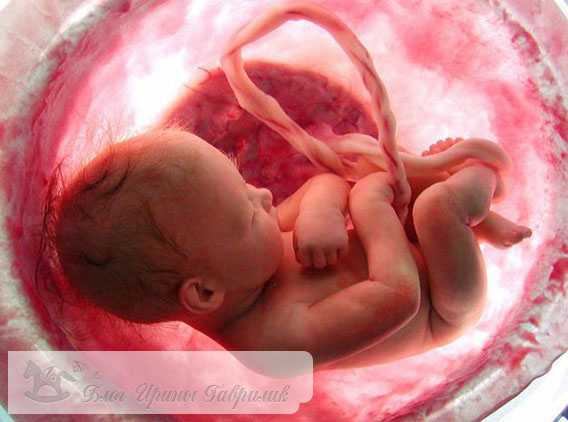

Развитие плода

Ваш малыш целиком и полностью уже подготовился для появления на свет. Абсолютно каждая из имеющихся систем, а также органов на 41 неделе беременности хорошо развиты. То есть малыш подготовлен для начала жизни вне утробы матери.

Внутреннее развитие. Как изменяются органы?

Абсолютно все органы такие, как почки, сердце, печень и иные, хорошо функционирую без каких-то препятствий. Легкие малыша накопили достаточно количество сурфактанта, вещества, которое помогает легким справляться с функцией дыхания. Кишечник заполняется первородным калом, который обязан выйти в первые дни после родоразрешения.

Развитие нервной системы приостанавливается, так как продолжение будет после рождения малыша. Крепнут голосовые связки. В ближайшем времени крики малыша привлекать внимание мамы. Кости черепа также твердеют, что иногда вызывает разрыв родовых путей женщины в процессе родов.

Оболочка плаценты, которая отделяют ребенка от женского организма, слабеет и делается проницаемой, что дает возможность материнской крови совмещаться с кровью малыша. Ребенок получает женские антитела, которые помогают защитить его организм от различных инфекций после родов. Подобным образом мама дает собственный иммунный опыт малышу.

Внешнее развитие плода. Как он изменяется в этот период?

На данном сроке ребенок будет выглядеть гораздо красивее, нежели несколько месяцев назад. Сейчас родовая смазка находится лишь на нежнейших местах – в подмышках и пахе. Пушок пропал, а волосы на голове и ногти на пальцах растут. По этой причине совершенно не удивительно, когда ребенок рождается с хорошей шевелюрой и отросшими ноготками.

Детские формы становятся более круглыми, а вот хрящи ушей крайне плотными. Малыш прибавляет в сутки как минимум по 30 грамм жира. Его кожа розовая и гладкая. Плод на 41 неделе беременности уже весьма подрос и ему совершенно не комфортно в животе. По этой причине малыш периодически ведет себя тише и совершает крайне мало движений. Но все-таки вы по-прежнему обязаны чувствовать не менее десяти толчков ежедневно.